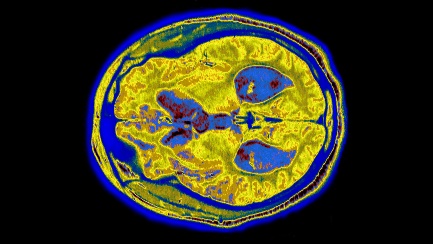

Các liệu pháp kháng thể mới có thể làm chậm quá trình thoái hóa thần kinh trong não của những người mắc bệnh Alzheimer. Nguồn: James Cavallini/Science.

Y học chưa có nhiều tác dụng đối với hàng chục triệu người mắc bệnh Alzheimer trên toàn thế giới và các phương pháp điều trị được phê duyệt chỉ nhằm mục đích điều trị các triệu chứng. Bộ não của những người mắc bệnh Alzheimer chứa các khối protein phức tạp, gọi là beta amyloid. Trong nhiều năm, các nhà khoa học đã tranh luận liệu việc loại bỏ chúng có giúp ích cho các bệnh nhân hay không. Kết quả một thử nghiệm kéo dài 18 tháng gần đây đã cho thấy, một phương pháp điều trị mới sử dụng kháng thể đơn dòng kháng amyloid có tên lecanemab, đã làm chậm quá trình mất nhận thức tới 27% so với giả dược. Đây là bằng chứng thuyết phục để các cơ quan quản lý ở Mỹ và Nhật Bản chấp thuận sử dụng liệu pháp này. Mùa hè năm nay, một nghiên cứu về phương pháp điều trị bằng kháng thể khác cũng nhắm vào amyloid não, được gọi là donanemab, cho thấy khả năng làm chậm sự suy giảm nhận thức tới 35% so với giả dược. Cả hai liệu pháp này đều được tiêm tĩnh mạch.